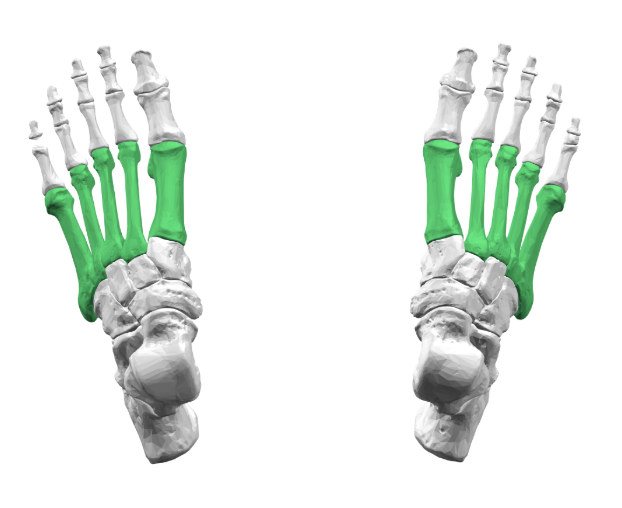

Proximal/Middle/Distal Phalanges - Foot

Phalanges

Metatarsals